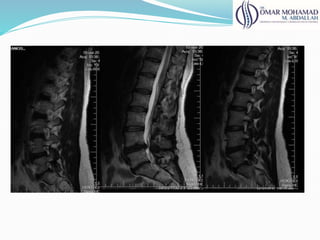

Rnm

● Melhor avaliação do disco e estruturas neurais;

● 100% de alt acima de 50 anos (lombar)

● 60% de alt acima de 60 anos (cervical)

● Correlacionar os achados com clínica

● Avalia: estabilidade, compressão e deformidades

61

Rnm ● Melhor avaliaçãodo disco e estruturas neurais; ● 100% de alt acima de 50 anos (lombar) ● 60% de alt acima de 60 anos (cervical) ● Correlacionar os achados com clínica ● Avalia: estabilidade, compressão e deformidades 61